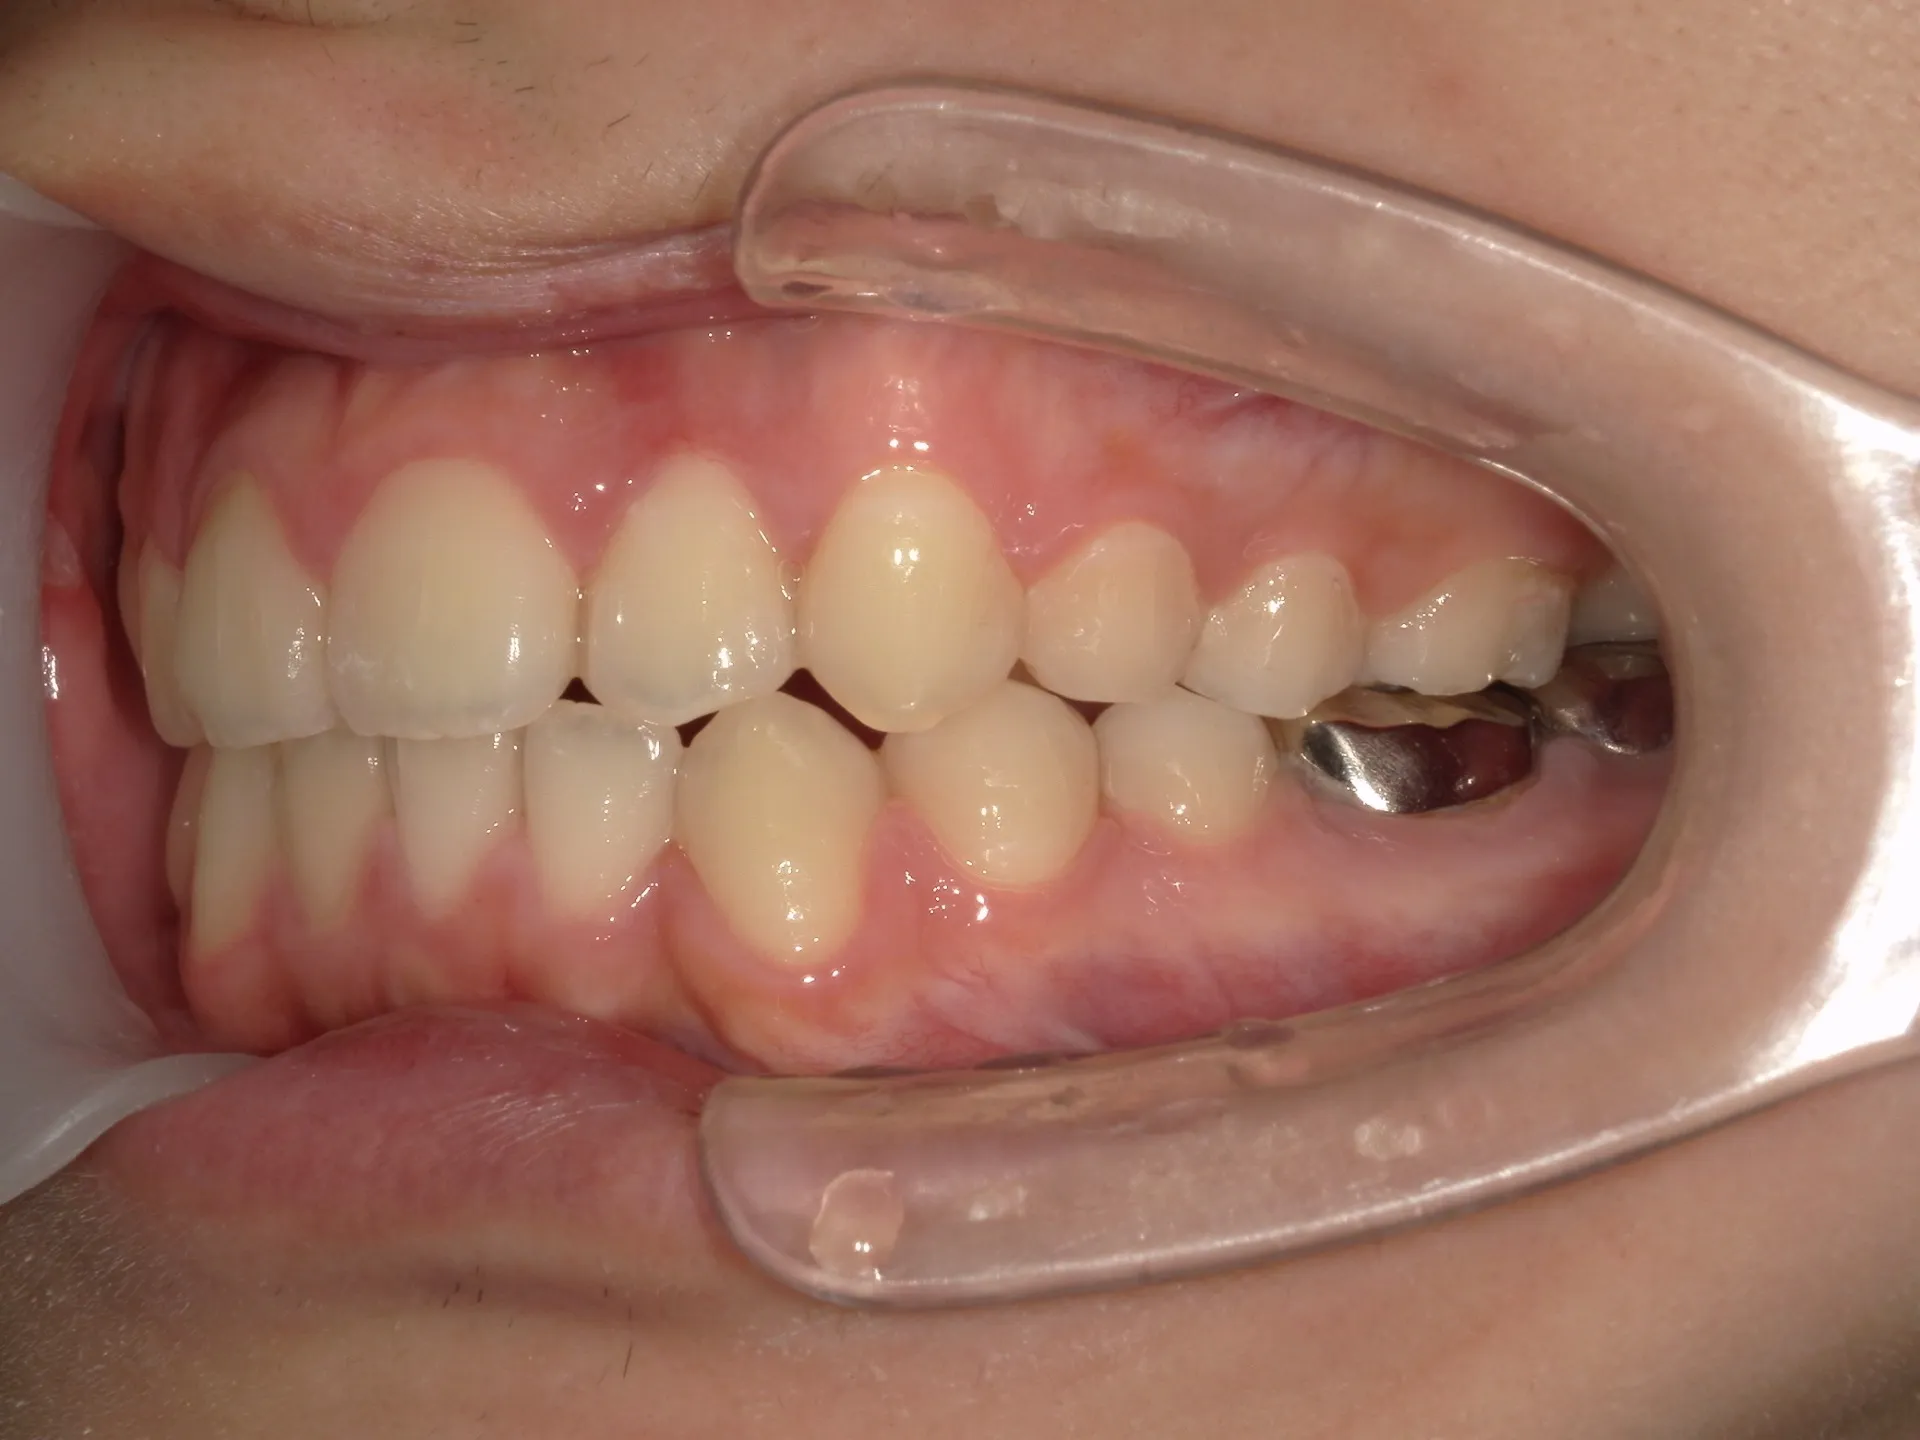

今回は下の前歯が1本ない場合の矯正治療についてご紹介いたします。